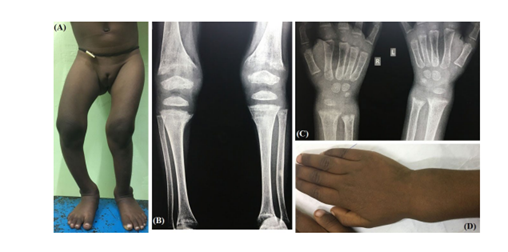

Hypophosphatasia, a condition associated with deficient function of alkaline phosphatase (ALP) enzyme, chronic systemic acidosis due to any cause, and drugs like bisphosphonate, fluoride, aluminium and parenteral iron are also associated with mineralization defects of the cartilages and bones. Serum calcium and phosphate concentrations are usually normal in rickets secondary to these conditions. Two most common disorders associated with metabolic acidosis and rickets are chronic kidney disease and renal tubular acidosis (RTA) (Figure 1).

Figure 1: 4-year girl with rickets due to dRTA. Note the ‘windswept’ deformity (A) and wrist widening (D). Typical radiological features like cupping, splaying, fraying and increased metaphyseal lucency are visible around knee (B) and wrist joints (C).